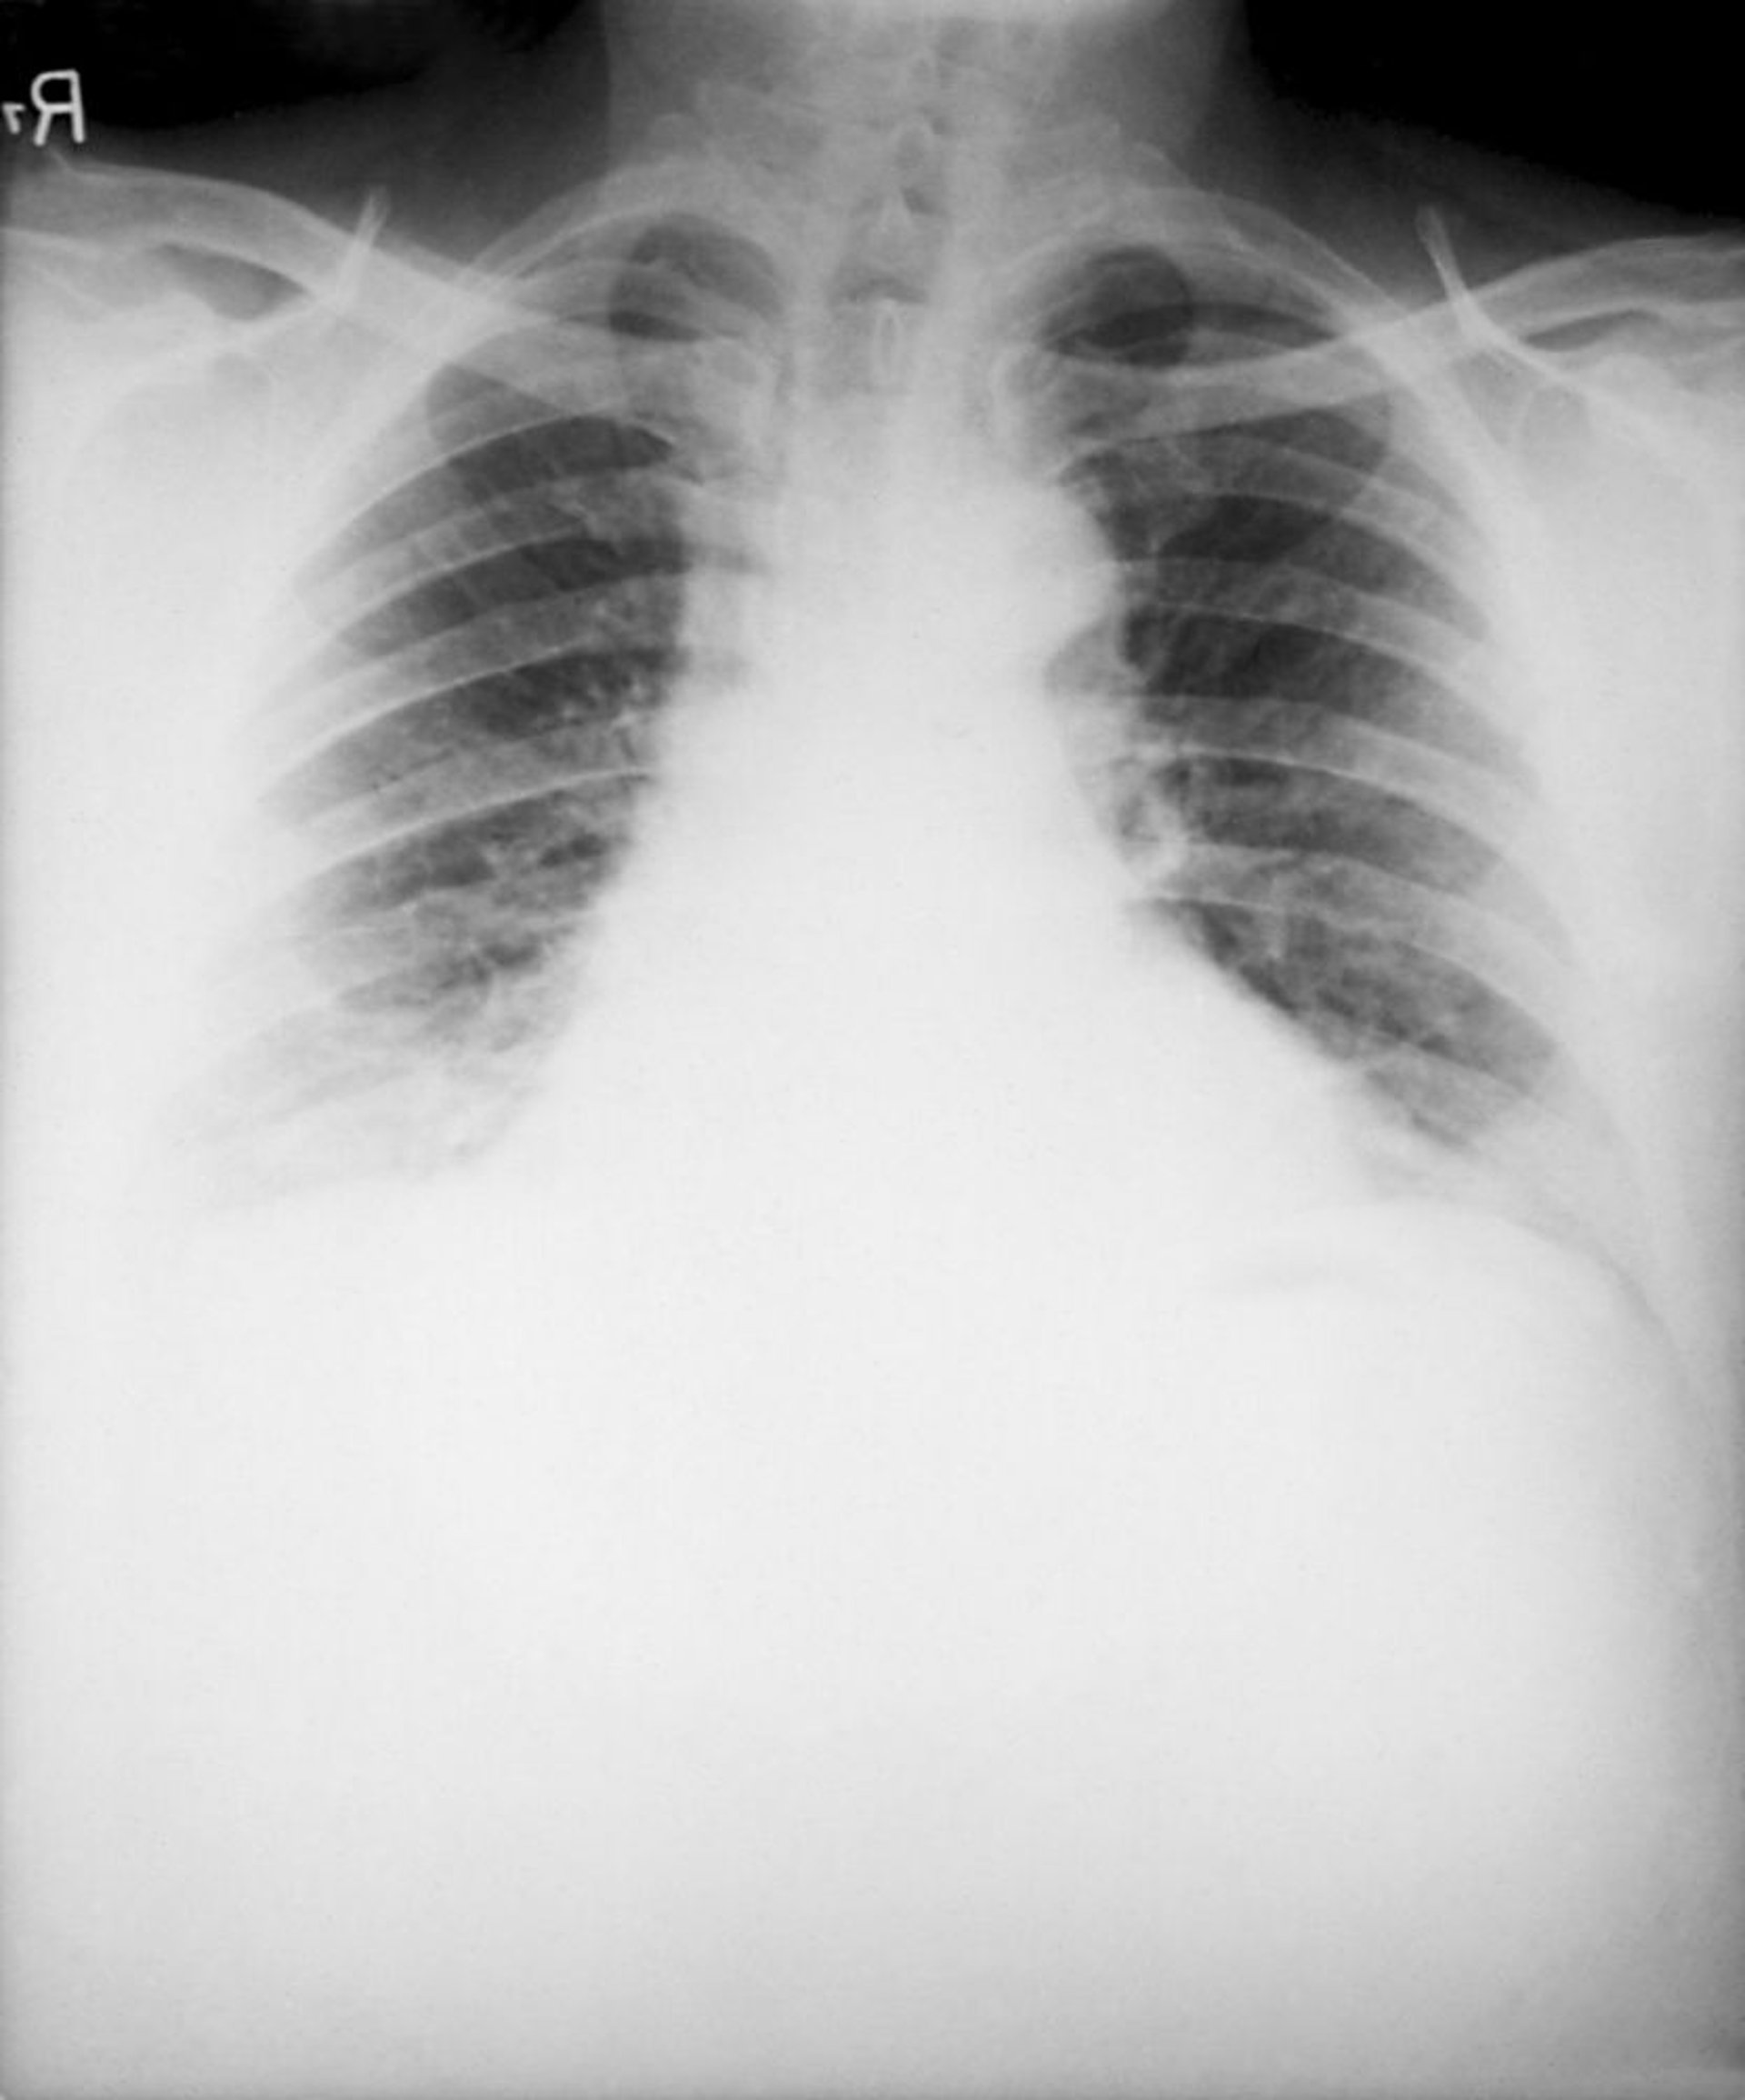

Charbon (anthrax) (inhalation)

Les signes typiques du charbon (anthrax) par inhalation sur la radiographie thoracique comprennent un médiastin élargi dû à une lymphadénite médiastinale nécrosante hémorragique et des épanchements pleuraux bilatéraux. Les infiltrats pulmonaires sont peu fréquents.

Image courtoisie de the Public Health Image Library of the Centers for Disease Control and Prevention.